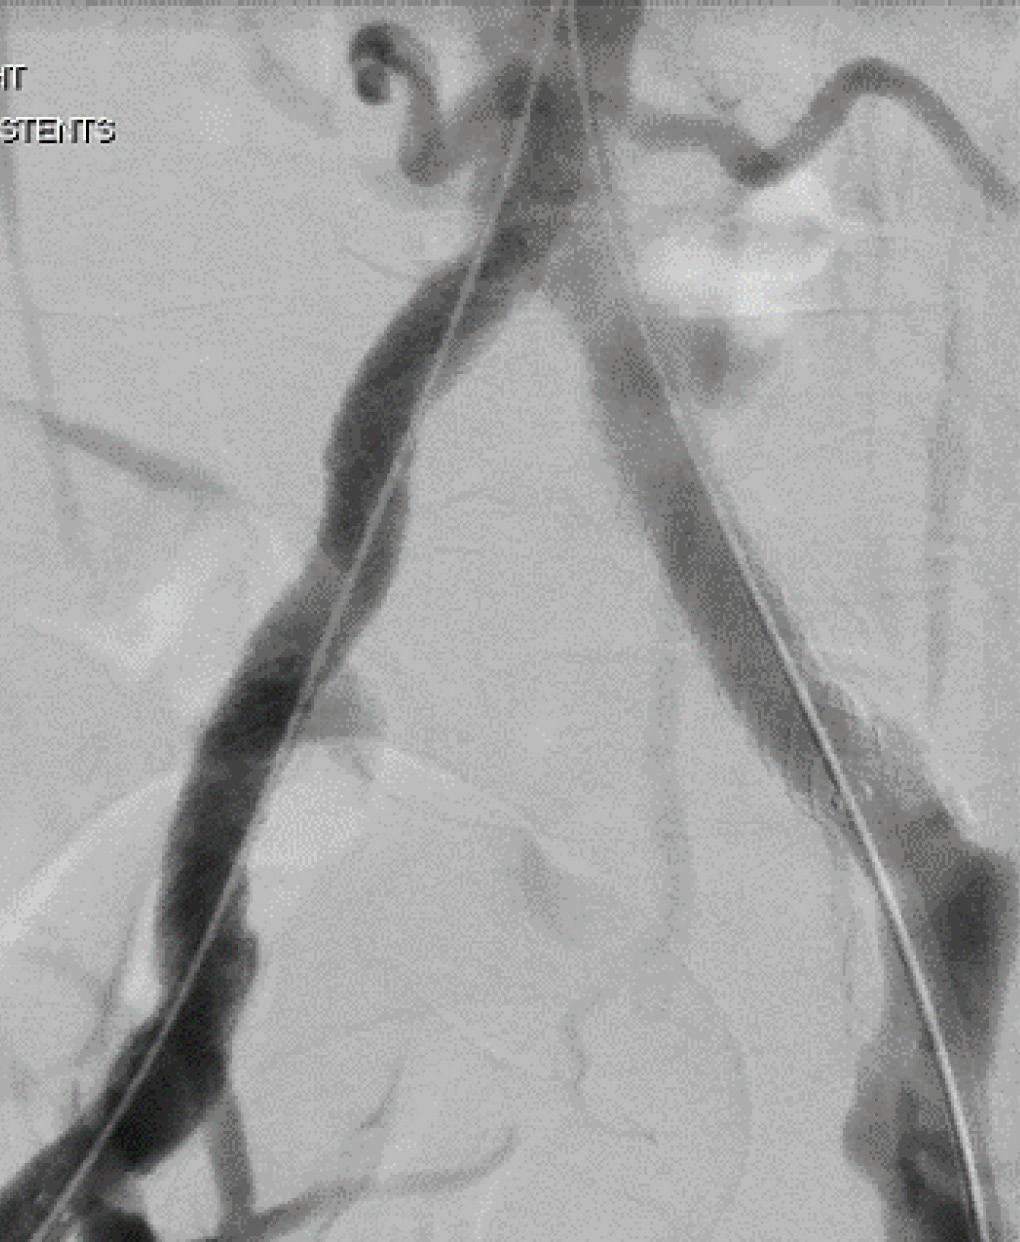

Reevaluating aortoiliac endarterectomy: Case series shows ‘acceptable durability’

THE UNCOMMONLY PERFORMED aortoiliac endarterectomy—one of the open procedures on which the vascular surgical specialty was founded— surgery provides acceptable durability in patients with smaller native vessels, especially among females, a 25-patient case series review performed at Louisiana State University (LSU) Health Sciences Center in New Orleans has shown.

Results from the analysis, presented at the 2024 Southern Association for Vascular Surgery (SAVS) annual meeting in Scottsdale, Arizona (Jan. 24–27) by Shivik Patel, MD, demonstrated freedom from major adverse limb events of 89% and 81% at two- and three-years post-procedure, while primary and secondary patency three years out were 86% and 89%, respectively.

The aortoiliac occlusive disease patient sample, from 2006–2022, was 72% female

with a mean age of 53.6 years. “Two of these patients had early post-operative thrombosis, and both of those patients had undergone procedures in an acute limb ischemia type of event,” explained Patel, a former vascular resident at LSU and now attending surgeon at WellSpan Health in York, Pennsylvania.

“Among the patients who underwent the procedure in an elective circumstance, there was one instance of late reintervention that was needed, but, overall, this series shows pretty durable outcomes after three years.”

A subanalysis involving mean aortic and iliac diameter measurements further demonstrated that the patient cohort had smaller native vessels than the means of a general population, Patel continued. “We went through all of the patients imaging and measured their juxtarenal aorta, their infrarenal aorta, distal aorta and bilateral

iliac arteries, as we wanted to compare our group to standard population means for the age group,” he said. “We saw that our aortic diameters and iliac diameters were less than those means.”

Patel conceded study shortcomings, principally the lack of a control group. “Our study involved most predominantly females, which could provide some bias in terms of having a mostly female sample, but I think it speaks to benefit something like this can have in the female population,” he added.

Patel argued that given the procedure’s relatively uncommon use in practice, the 25-patient sample provides a “fairly robust” dataset with which to introduce numbers suggesting a role among a specific patient group.

“We have noticed, especially in my clinical experience, in patients in whom we place stents in their smaller vessels, they are not going to have the durability, and, down the road, you’re going to be placing a aortobifemoral bypass,” he noted. “If you have a reason to avoid a large prosthetic graft, as in an aortobifemoral graft, or avoiding femoral incisions, this is a very durable procedure to

do if you have isolated aortic and iliac disease, as long as the patient has acceptable operative risk.”

Patel sees his dataset, for a procedure first performed in the early 1950s, and described in a 2006 Annals of Vascular Surgery paper as “almost a lost art,” as a moment for repose. “This is an opportunity for us to reevaluate one of the traditional operative techniques our specialty is founded on and to make sure we don’t forget about procedures like it,” he said. “They may come back to play a role, and aortoiliac endarterectomy is a surgery I think may re-emerge as a more popular option in patients with specific anatomic specifications.”